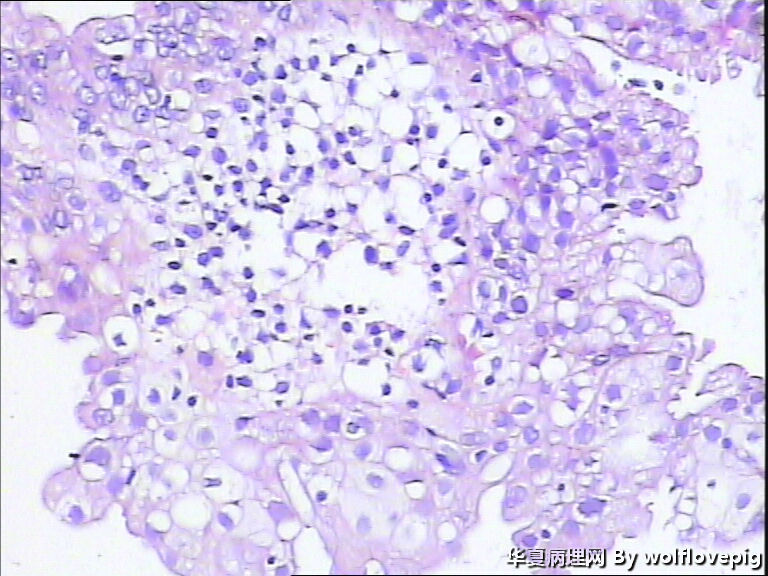

40y,阴道不规则流血10+天

流血期子宫内膜,这些变化都是化生,不怕

分泌期宫内膜伴嗜酸细胞化生

乳头状化生,嗜酸细胞化生,透明细胞化生

分泌期宫内膜伴嗜酸细胞、乳头状化生

医源性改变(药物等)。

是一种化生性改变,问题不大。